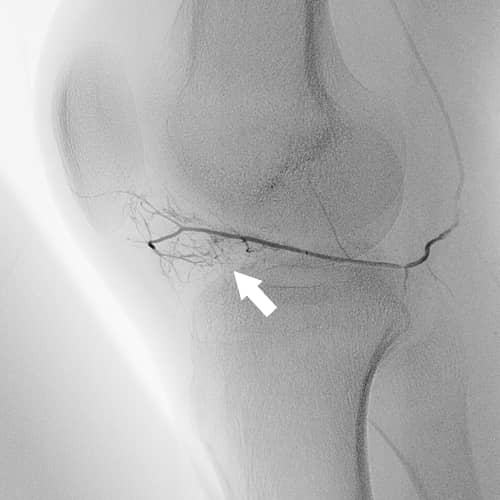

知っておきたい!ひざ下の痛みの原因とは

[記事提供:オクノクリニック | モヤモヤ血管による慢性痛治療(https://okuno-y-clinic.com)]…